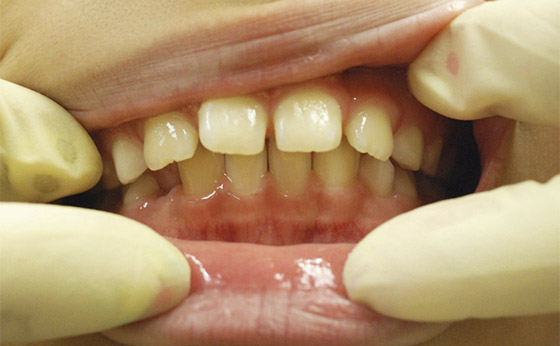

途中経過03

それから半年で永久歯に生え変わりましたが、前歯が開いてしまいました。

途中経過04

その後は簡単な矯正装置で修正、半年でここまで改善いたしました。